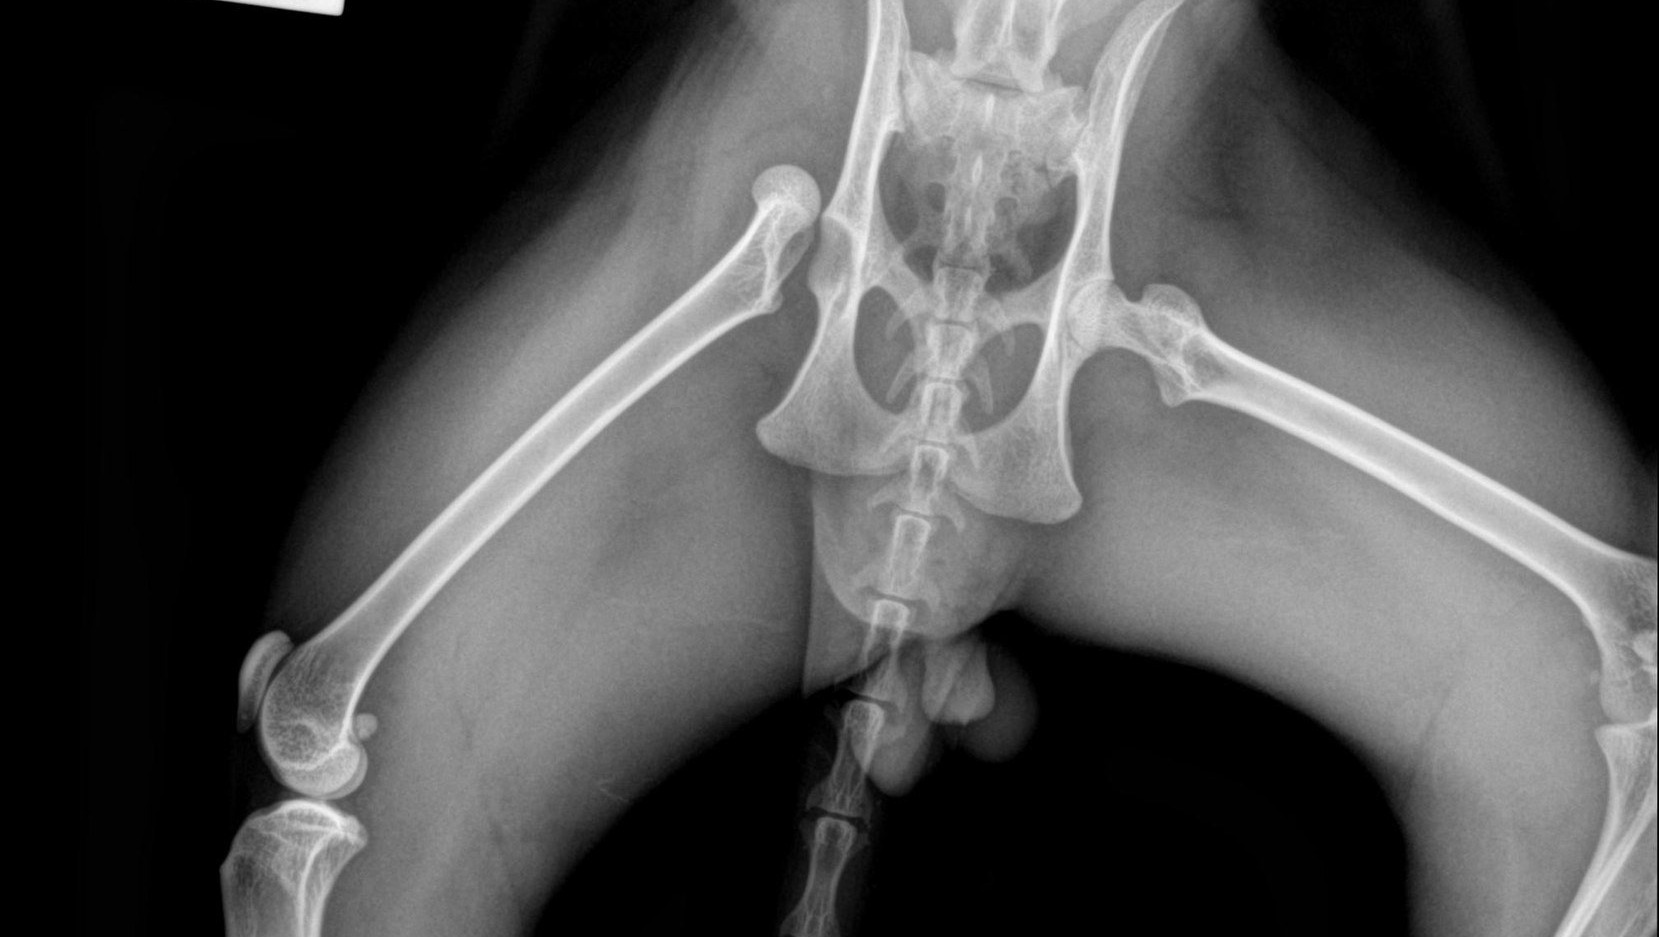

Elvis was found after being hit by a car, suffering an extremely painful dislocated femur. With no microchip and no owner identified, we stepped in to make a life-changing decision: amputate his leg or attempt complex orthopaedic repair.

Although amputation would have been the less costly option, we chose to pursue surgery to save his leg, giving Elvis the best possible chance of long-term mobility and quality of life. The surgery was successful, but his recovery requires ongoing monitoring, medication, and follow-up procedures.

We were faced with a heart-breaking decision: amputate or attempt complex surgery to save Elvis’s leg.

Amputation would have been quicker and far less expensive. But after specialist advice and careful consideration, we chose to fight for his leg.

Choosing to save his leg means advanced orthopaedic surgery and a carefully managed recovery. It also means a vet bill currently estimated at over £3,000. We believe he deserves the option that gives him the best long-term comfort, mobility, and dignity - not simply the cheapest solution.